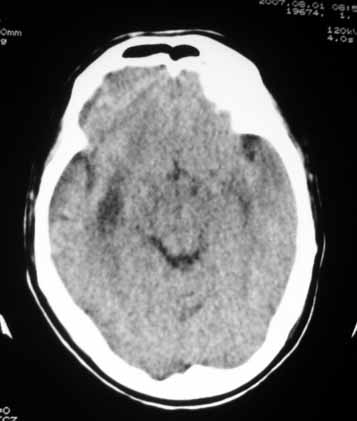

1、右侧外囊区脑软化;

2、左侧额、顶、枕区脑转移瘤。

1、右侧外囊区脑软化.

2、左侧额、顶、枕区脑转移瘤.

考虑:1、左侧额、顶、枕区脑转移瘤;

2、右侧外囊区脑软化。

脑内多发结节性小病灶,周围水肿明显,结合结肠癌病史,典型的转移瘤。